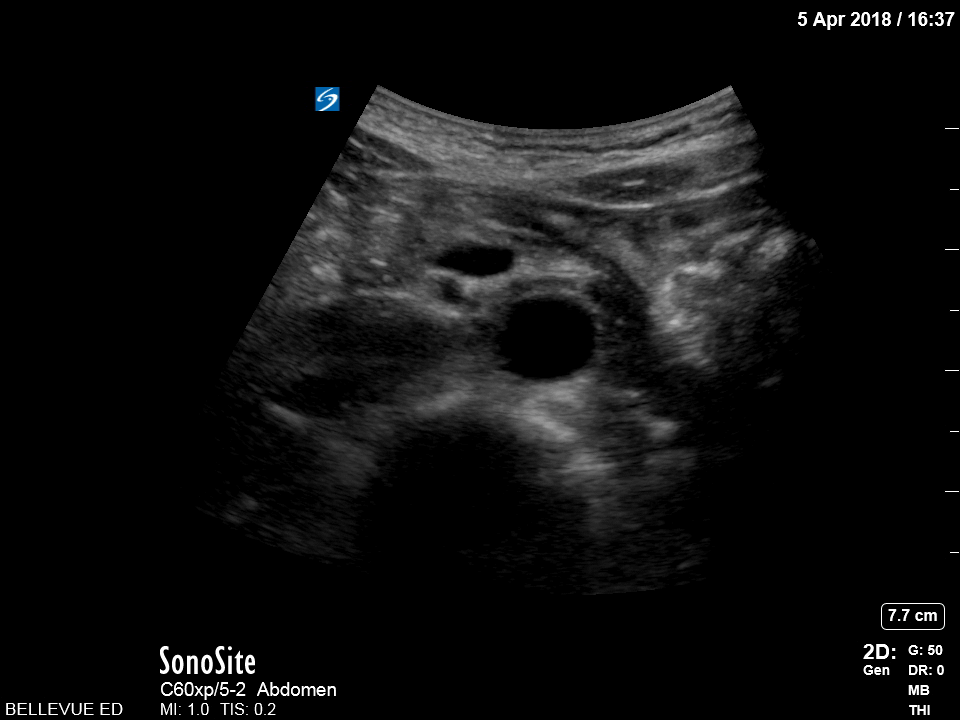

Distal Aorta Orange: Spine, Red: Aorta and Iliacs, Blue: IVC, Green: Portal venous confluence, Pink: “Seagull sign” aka celiac trunk Images: Dr. Lindsay Davis, Dr. Hannah Kopinski. Image Editing: Michael Amador and Dr. Matthew Riscinti